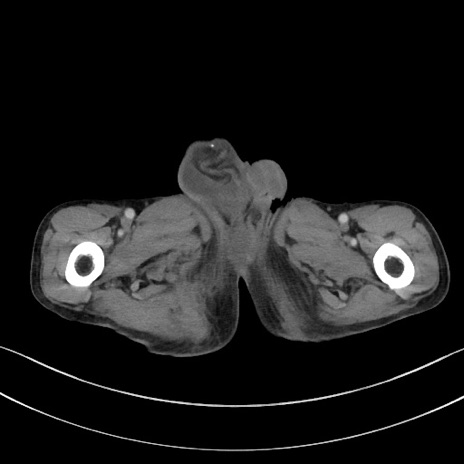

冠状断像

矢状断像